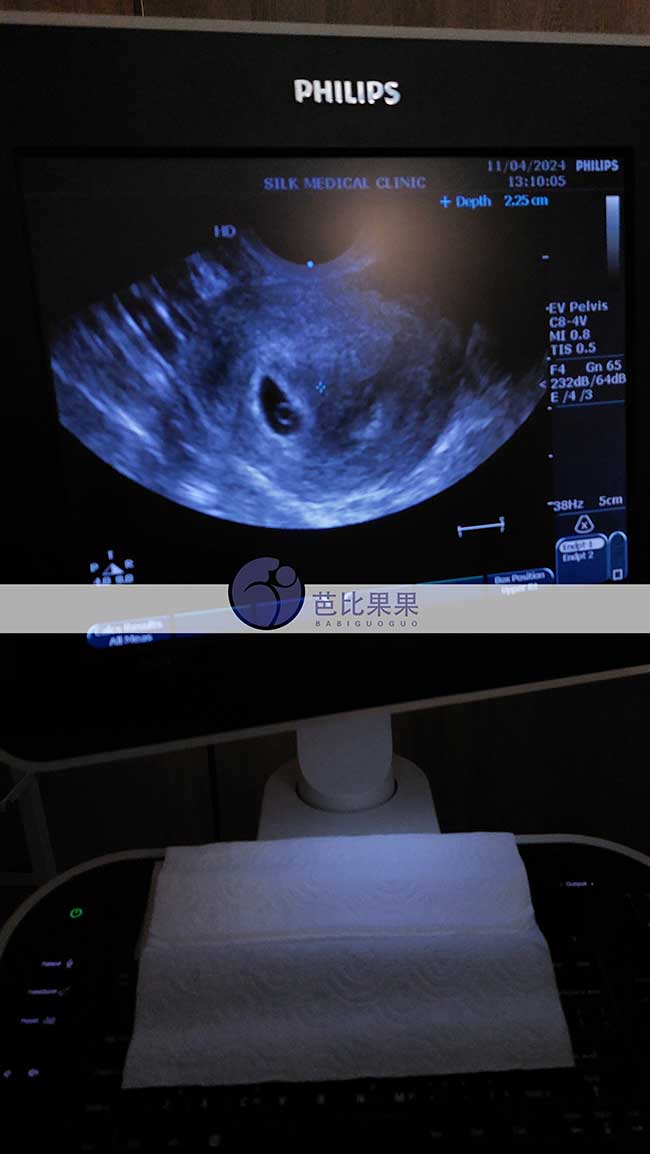

浙江X女士试管助孕匹配的哈克斯斯坦试管妈妈做首次B超孕检

浙江X女士子宫内膜太薄无法自怀生子选择到格鲁吉亚试管助孕,匹配到的哈克斯斯坦试管妈妈成功验孕后在第比利斯做首次B超孕检,大概5-6周,检查宫腔内可见一个妊娠囊。